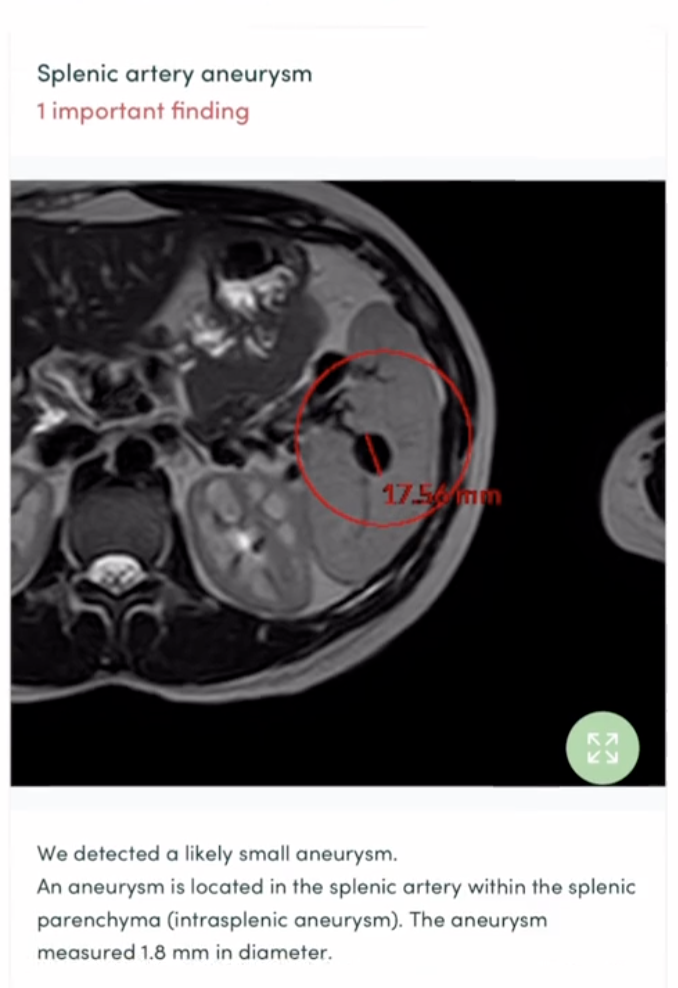

Four days later, Sarah got the bad news. She said, “I had nobody to call. I just went into a full-blown panic attack when I got my results and ended up in the emergency room because I needed a doctor to tell me what this meant.”

She continued, “I got a CT scan. There are actually two aneurysms inside of my splenic artery. Now I am getting my spleen removed.”